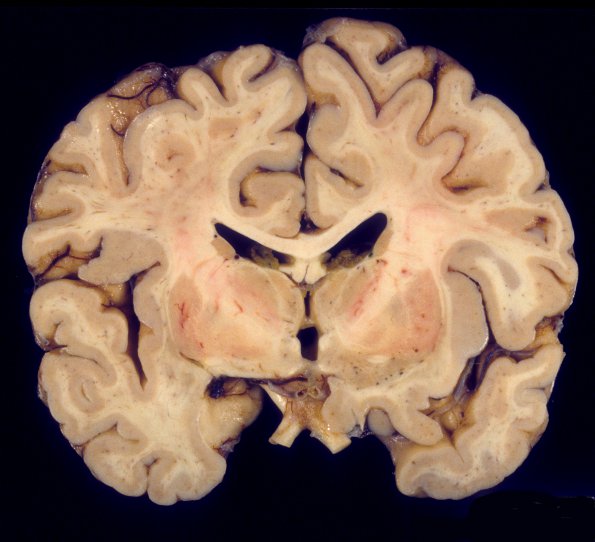

HIV Encephalitis

4A2 HIVL (& lesser HIVE) (Case 4) 1A

This coronal section shows mild sulcal expansion and dilatation of the lateral ventricles.